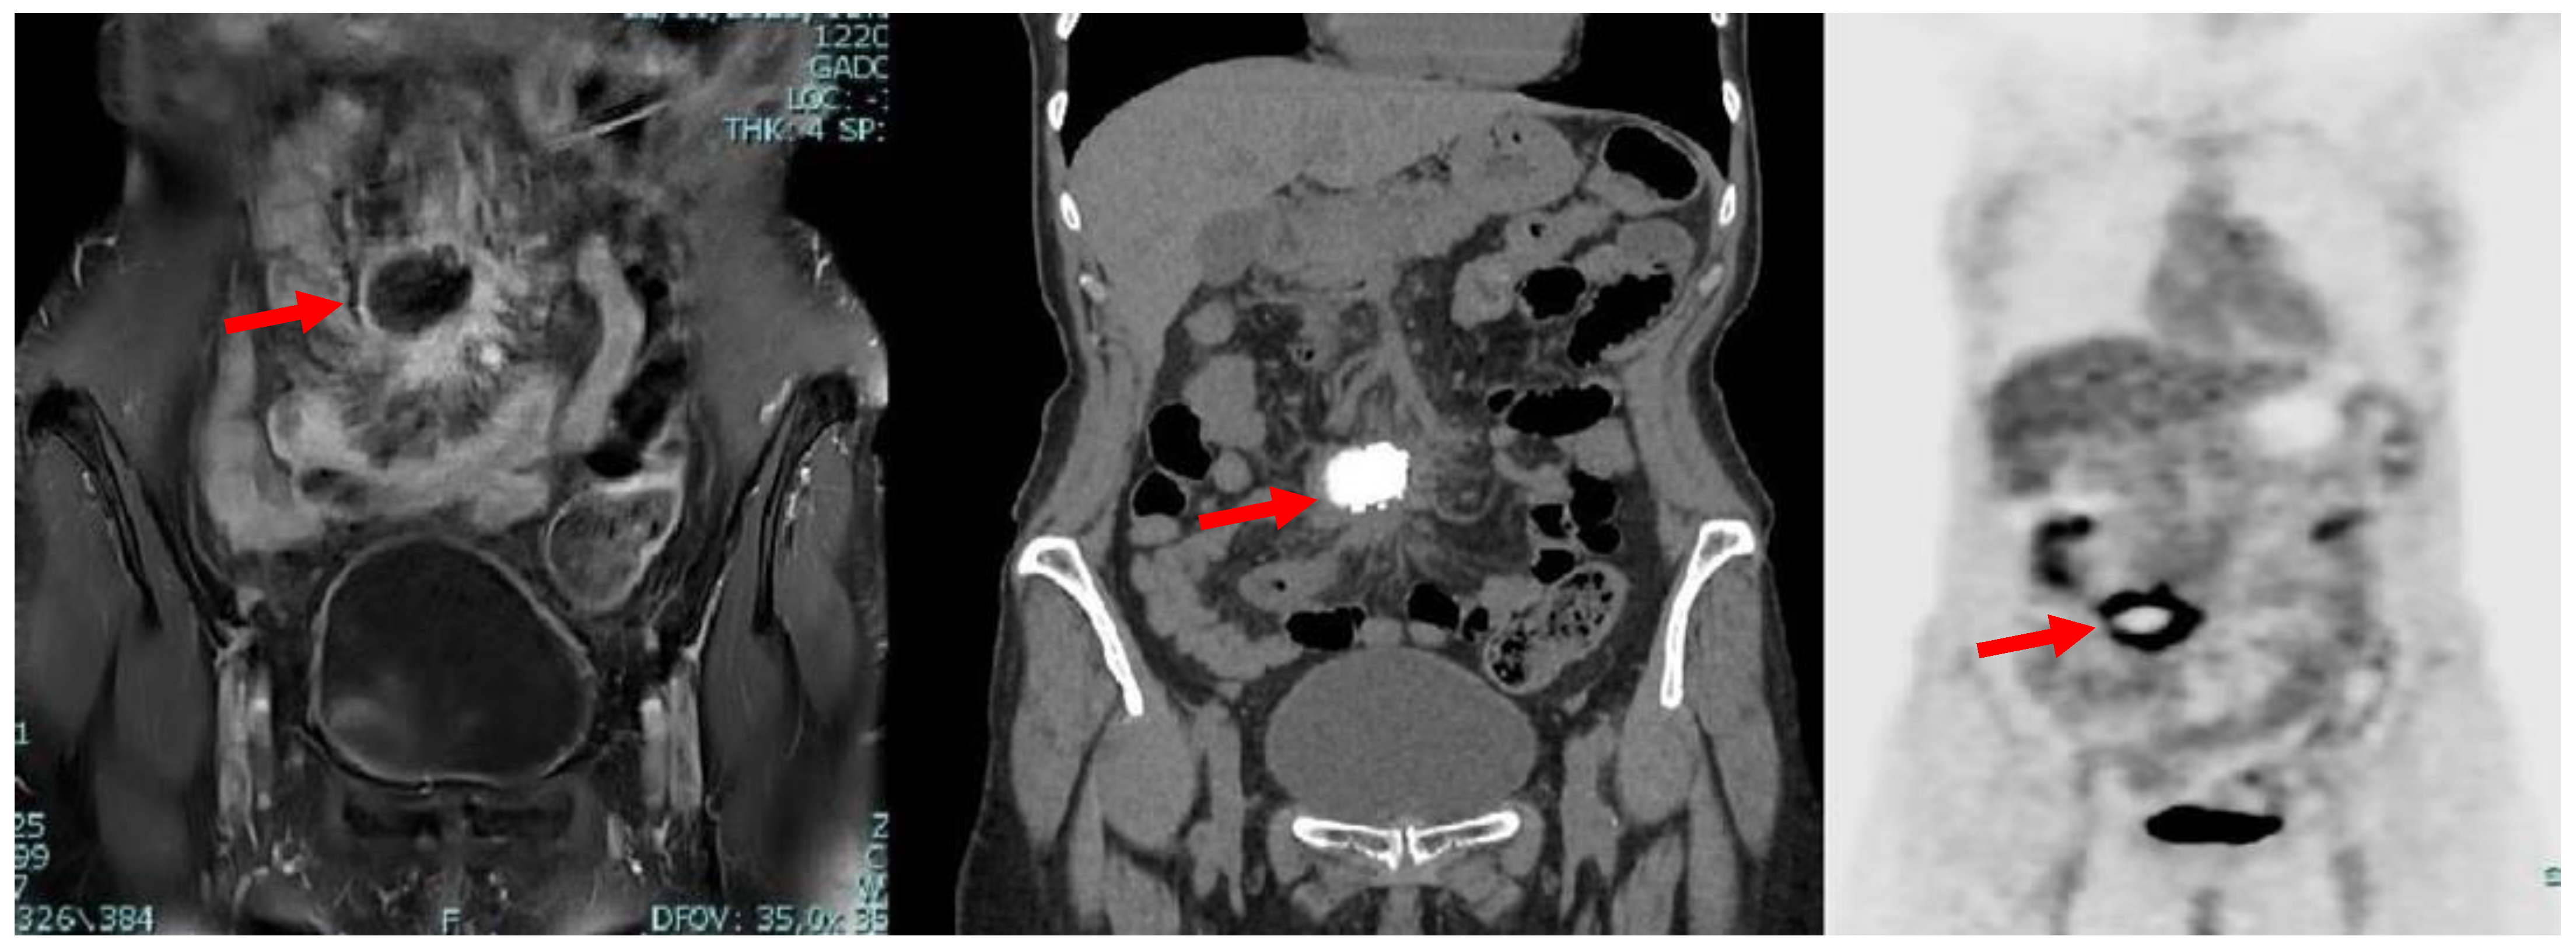

Due to iodinated contrast agent allergy, the patient underwent abdominal contrast-enhanced magnetic resonance imaging (CE-MRI) scan complete with computed tomography (CT) scans documenting, in the hypogastrium, the presence of voluminous multilobular lymphadenopathies (about 45 mm of maximum diameter) with calcific nucleus surrounding the mesenteric vessels and infiltrating the mesenteric fat (Figure 1).

Figure 1.

Axial MRI (left) and CT (right) scan showing the presence, in mesogastrium, of a nodular mass (red arrows) with contrast enhancement at MRI and internal calcifications at CT.